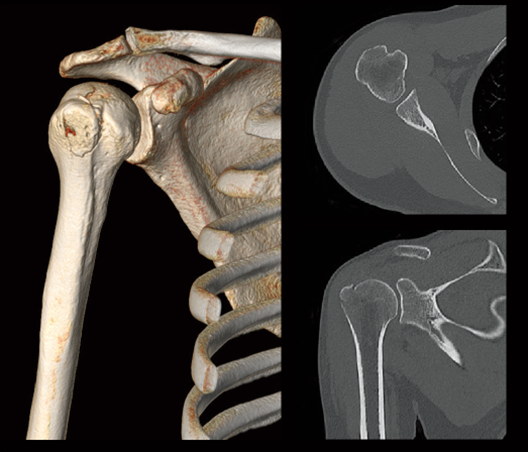

Fractura por tuberosidad mayor en el húmero